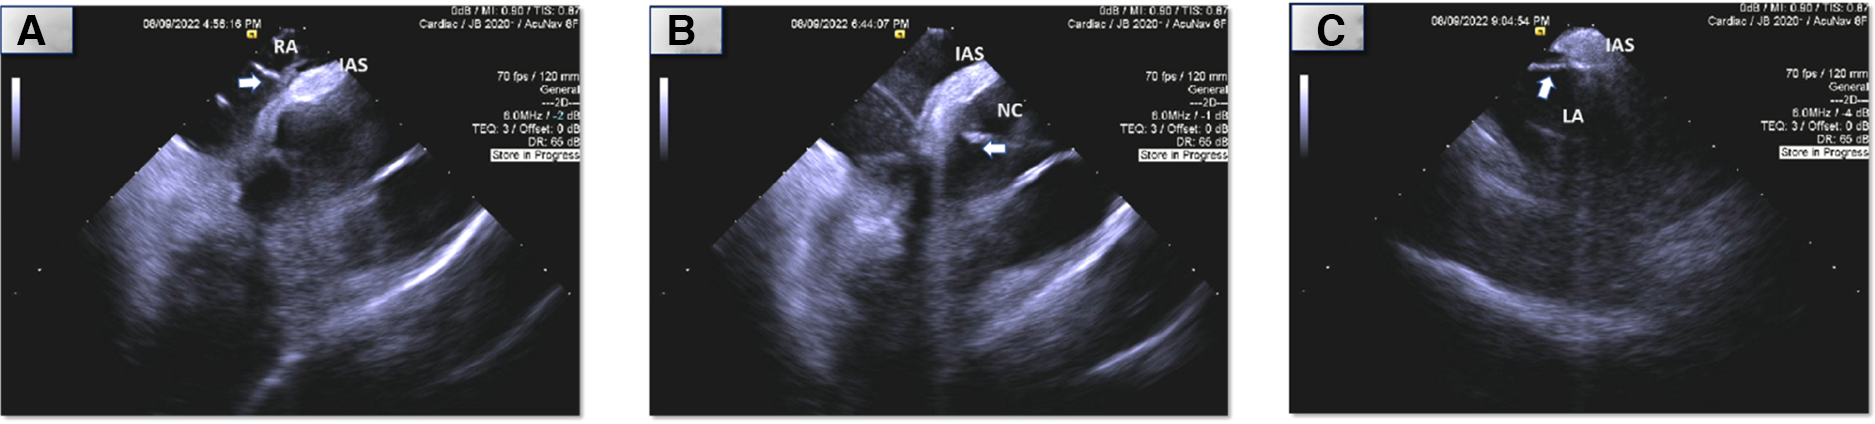

Figure 3

Intracardiac (ICE) echocardiography of ablation sites (arrow: ablation catheter, RA, right atrium; NC, non-coronary sinus of Valsalva; LA; atrial septum; IAS, interatrial septum). *Images are placeholders for videos which are attached. (A) Right atrial septum. (B) Non-coronary sinus of Valsalva. (C) Left atrial septum.

Using an irrigated catheter (ThermoCool SmartTouch, Biosense Webster, Irvine, California), ablation was performed at the earliest site (Figure 2A shows electrograms during tachycarida, Supplementary Figure S2A shows same site during sinus rhythm) using radiofrequency energy of 30–40 Watts with 30 cc/minute flow for 30–90 s per lesion. We noted almost immediate suppression of the tachycardia with ablation (Figure 3A shows catheter position during ablation with intracardiac echocardiography; Supplementary Figure S3A shows corresponding fluoroscopic position). We then performed additional lesions around this region, in particular targeting the muscle bundle opposing the non-coronary aortic sinus of Valsalva and superior limbus. Despite extensive ablation around this area, the tachycardia continued with a similar cycle length.

We then performed mapping of the opposite side of the septum in the non-coronary sinus of Valsalva which was not particularly early. We did position our catheter slightly higher in order to be adjacent to the prior lesions from the right atrium and noted atrial electrograms −17 ms ahead of the surface p wave (Figure 2B shows electrograms during tachycarida, Supplementary Figure S2B shows same site during sinus rhythm). Radiofrequency lesions were performed in this region at 30–40 Watts and 30 cc/min flow for 30–60 s per lesion (Figure 3B and Supplementary Figure S3B shows corresponding intracardiac echocardiography and fluoroscopic position of ablation catheter). Despite this, the tachycardia persisted, and we returned to the right atrium and performed additional radiofrequency ablation lesions in the same location along the septum as before. We noted transient suppression of tachycardia but afterwards we noted recurrence. Despite the use of a long sheath, some catheter movement was noted during ablation. To achieve better stability, we exchanged the radiofrequency ablation catheter for a cryoablation catheter (Medtronic CryoCath LP, Pointe-Claire, Canada), and created several lesions (freeze-thaw-freeze cycles to −80° Celsius for 3–4 min per lesion) along the superior limbus region. Despite initial suppression, AT recurred thereafter. This prompted transseptal access to map the left atrium. Mapping of the atrial septum was performed which revealed earlier (−29 ms relative to surface p wave) and fractionated signals near the left side of the superior limbus (Figure 2C shows electrograms during tachycarida, Supplementary Figure S2C shows same site during sinus rhythm) and close to the right superior pulmonary vein along the roof (directly adjacent to the area where right atrial ablation was performed). A series of ablation lesions were created using radiofrequency energy at 30–35 Watts and 30 cc/min flow for 30–60 s per lesion (Figure 3C shows corresponding ablation catheter position with intracardiac echocardiography; Supplementary Figure S3C shows corresponding fluoroscopic position). We noted temporary suppression and slowing of the tachycardia.